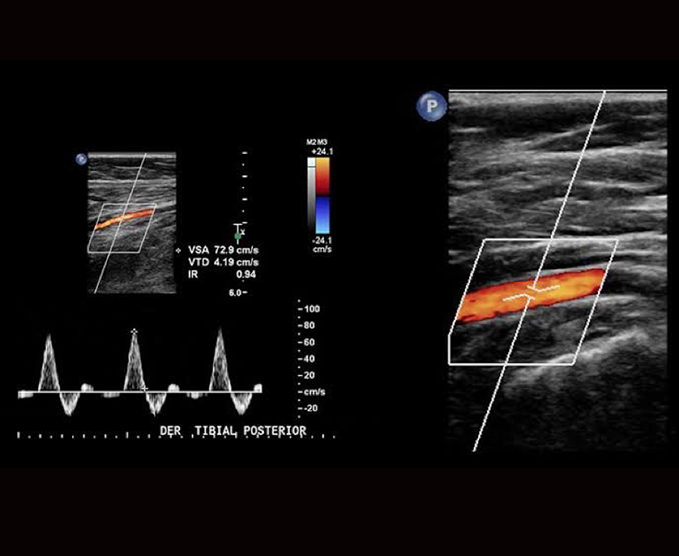

Ecografía Doppler

El Doppler es un tipo especial de ecografía que brinda la posibilidad de ver y estudiar las ondas de velocidad de flujo de ciertas estructuras del cuerpo, como los vasos sanguíneos, por lo que se utiliza para estudiar las arterias, venas y la vascularización de los órganos.

- Doppler arterial